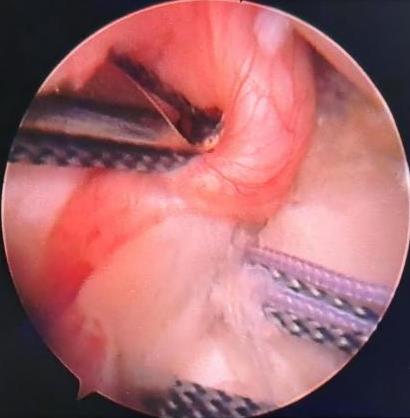

• 宫腔镜联合钳夹术与宫腔组织切除动力系统治疗胚物残留的临床效果对比

摘要:目的 比较宫腔镜联合钳夹术和组织切除动力系统治疗胚物残留(RPOC)的临床效果。方法 回顾性分析2023年1月-2024年12月该院因RPOC行宫腔镜手术的53例患者的临床资料,根据手术方法不同,分为联合钳夹组(n = 30)和组织切除组(n = 23)。比较两组患者术中和术后情况。结果 两组患者手术完成率分别为96.7%和95.7%,差异无统计学意义(P > 0.05);联合钳夹组手术时间较组织切除组长,术中出血量和器械插入次数较组织切除组多,差异均有统计学意义(P < 0.05)。两组患者均未发生并发症。两组患者膨宫液使用量、术后2周测量内膜厚度及月经情况比较,差异均无统计学意义(P > 0.05)。结论 宫腔镜组织切除动力系统治疗RPOC,较常用的联合钳夹术创伤小,效率更高。值得临床推广应用。